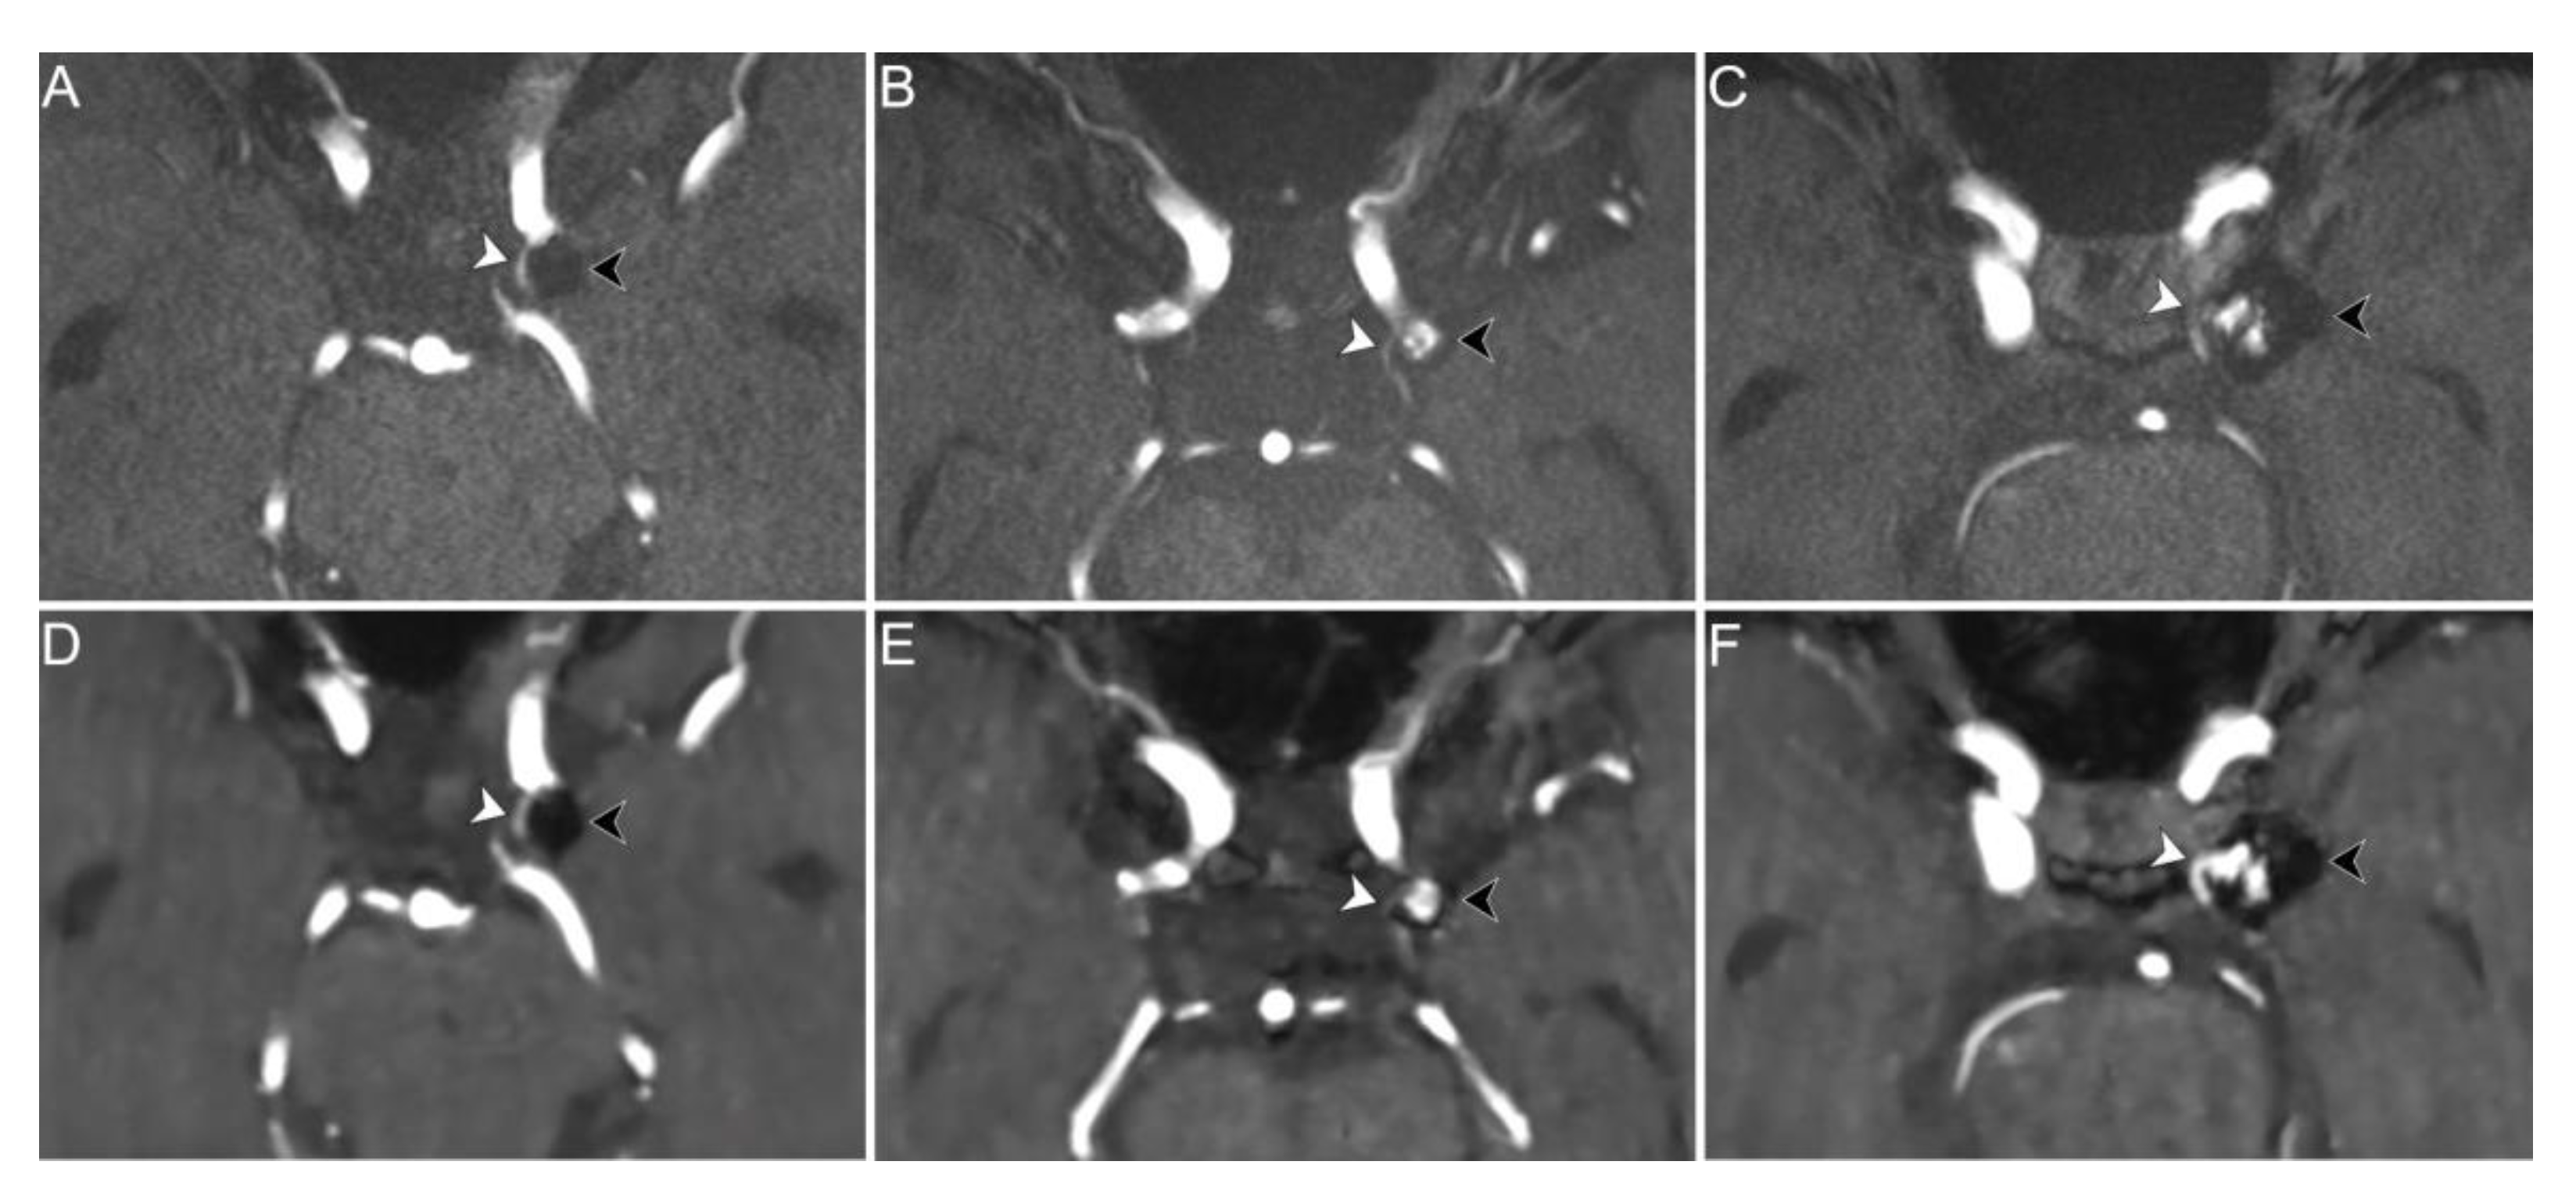

The depiction of vessels originating from the aneurysm neck or coursing in close proximity to the aneurysm dome in CS TOF images compared to PI TOF images was evaluated to be better in 8 readings (9.1%), equal in 70 (79.5%), and worse in 10 (11.4%) (Figure 4). No significant differences were found in CS TOF performance between patients with and without stent placement (p = 1, Table 2). Inter-rater agreement for the evaluation of vessels adjacent to the aneurysm was moderate (κ = 0.42, p < 0.001).

Figure 4.

PI (upper row) and CS (lower row) TOF MRA images of three different patients exemplifying differences in performance between the two sequences in the depiction of parent vessel and vessels coursing in close proximity to the aneurysm dome. Axial PI TOF MRA (A) and CS TOF MRA (D) of a coiled aneurysm of the left supraclinoid internal carotid artery (black arrowheads) without signs of recanalization (class I); the proximal portion of the left anterior choroidal artery, which courses in close proximity to the aneurysm dome, is equally visualized on both sequences (white arrowheads). Axial PI TOF MRA (B) and CS TOF MRA (E) of a coiled aneurysm of the left supraclinoid internal carotid artery (black arrowheads) with recanalization of the aneurysm neck (class II); the proximal portion of the left anterior choroidal artery, which originates from the aneurysm neck, is better depicted by the PI TOF image (white arrowheads). Axial PI TOF MRA (C) and CS TOF MRA (F) of a coiled aneurysm of the left supraclinoid internal carotid artery (black arrowheads) with flow signal between the coils (class IIIa); the proximal portion of the left posterior communicating artery, which originates from the aneurysm neck, is better visualized in the CS TOF image (white arrowheads).

When considering the evaluation of the parent vessel and vessels coursing close to the aneurysm dome, we found that CS TOF MRA performed equally or better than PI TOF MRA in 97.8% and 88.6% of cases, respectively. The only two patients in whom the parent vessel was better visualized on the PI TOF images were treated with stent assisted coiling for aneurysms originating from the anterior communicating artery and the pericallosal artery. Nonetheless, in 89.3% of readings the parent vessel was equally visualized on both sequences and in one case it was better depicted on CS TOF images. Previous studies showed that CS TOF MRA may result in worse visualization of smaller vessels compared to PI TOF MRA [21,28], therefore our results could be better explained by the small diameter of the stented vessels rather than the presence of susceptibility artifact due to the stent itself. This hypothesis is also supported by the observation that in the majority of cases in which CS TOF images showed a worse depiction of vascular structures adjacent to the aneurysm dome, the affected vessel was the anterior choroidal artery, which has a smaller diameter compared to the other examined vessels (Figure 4B,E). Nonetheless, further studies including a greater number of patients treated with stent placement are needed to assess the performance of CS TOF MRA in the evaluation of stented vessels.